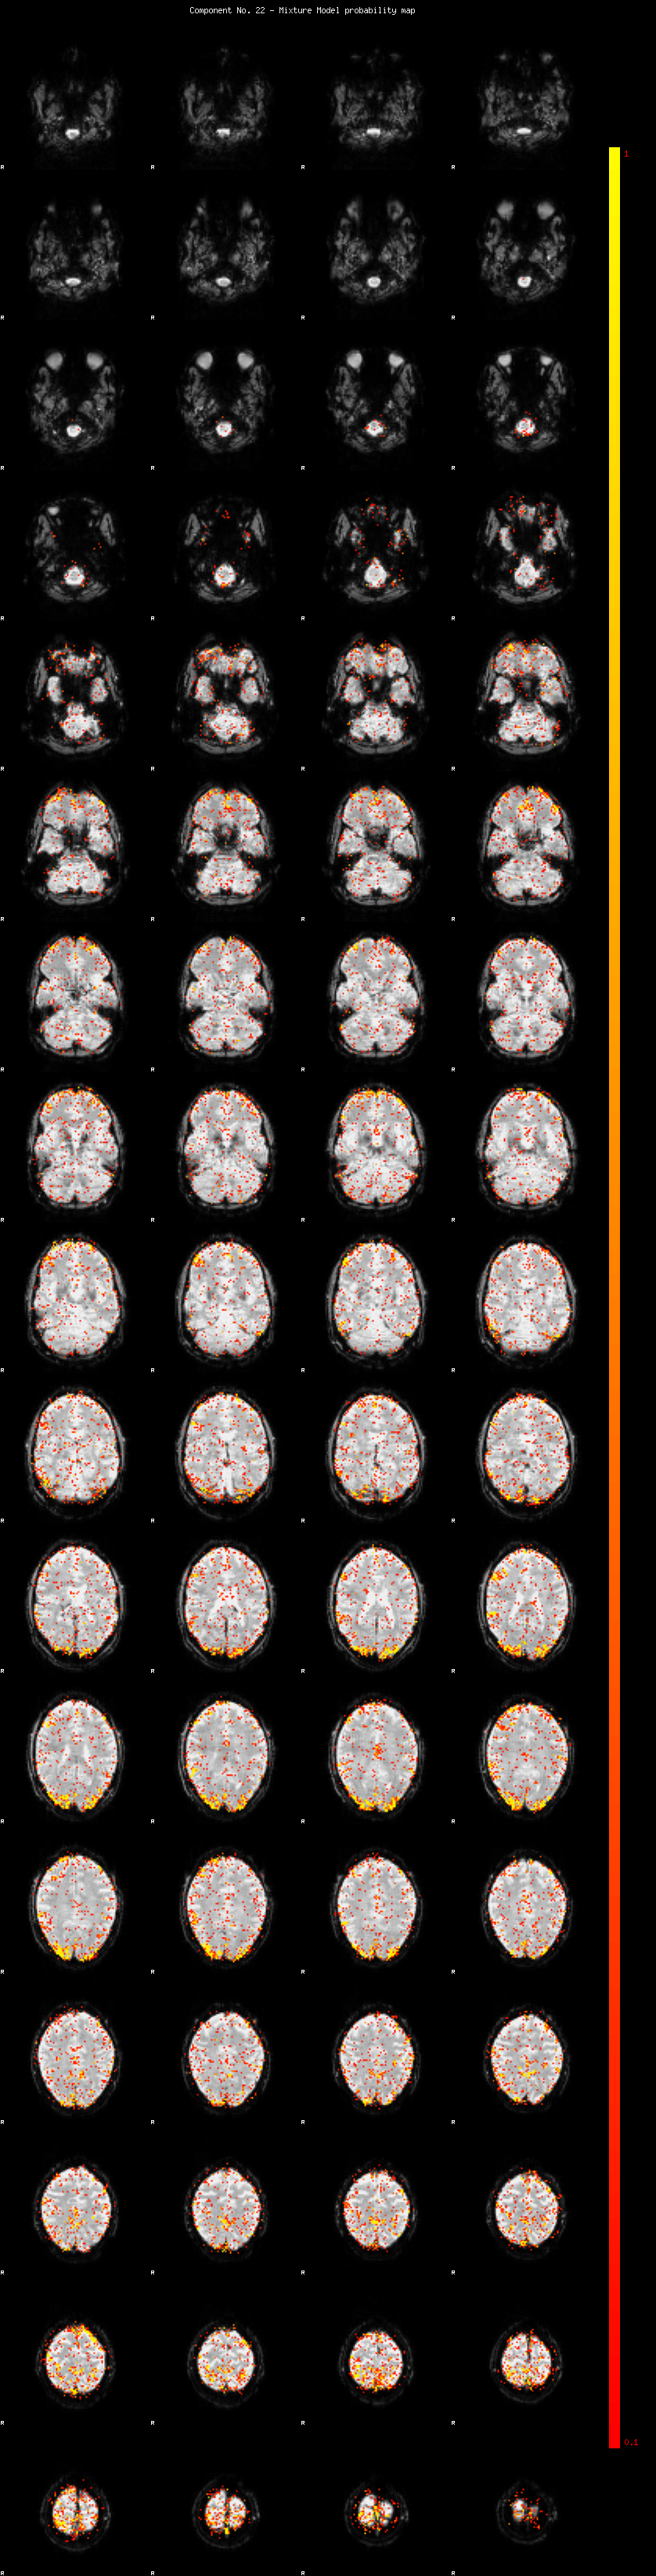

IC_22 Mixture Model fit

Means : -0.000000 2.829961 -2.729691

Vars : 1.000000 3.244758 1.171494

Prop. : 0.945495 0.038927 0.015578